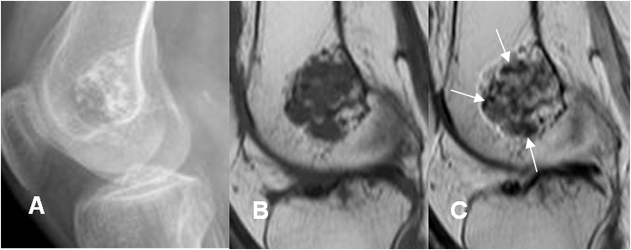

Fig 89 B. Encondroma.

A: Rx lateral. Imagen ovalada y con calcificación condroide de la matriz por encondroma.

B: RM sagital en T1 simple y C: RM sagital en T1 con contraste. La lesión muestra realce

heterogéneo del contraste y zonas hipointensas en su interior, que corresponden a las calcificaciones. (Flechas).